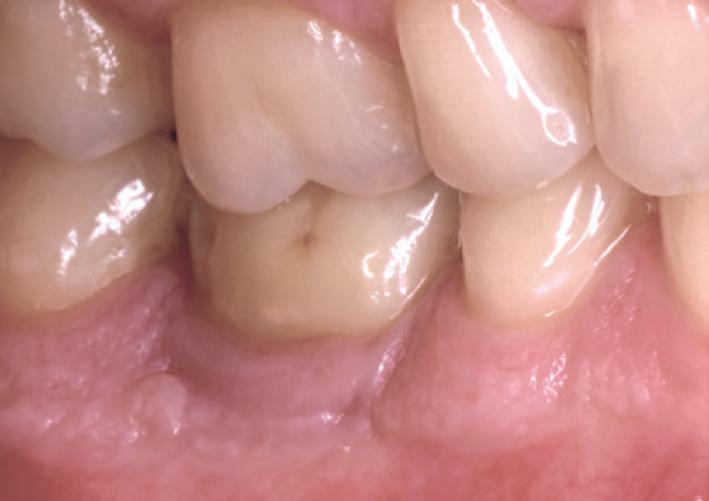

In 1975, one of my patients who was 18 years old became involved in a car accident; he hit the steering wheel with his chin and sustained 2 horizontal fractures in his 31, both quite a way subgingivally. The 41 and 32 were intact. The normal treatment at that time would have required extraction of the 31 and the placement of a partial denture or a bridge to replace the missing tooth.

Knowing that he had nothing to lose, he agreed to let me experiment on him. I extirpated the 31, drilled 10mm past the apex using a sterile Kurer Post spiral drill that matched the diameter of my titanium wire. I sterilised the Titanium using a

Yes, I did stick my neck out, but the result ended being a lot better for the patient than if we had opted for a bridge or a partial denture. The biological cost was negligible and we bought him 30 years of function until a better and more modern treatment became available.

In the current regulatory environment, treatment such as I described is not only illegal and would result in crippling fines being imposed by the TGA, but possibly result in losing one’s right to practice. If I had made a conventional bridge, the teeth either side would have been compromised and possibly lost by now, a partial denture would have caused periodontal problems.